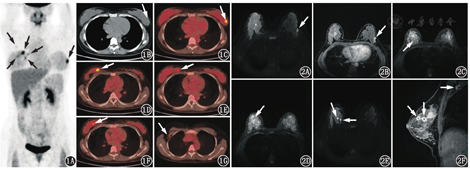

患者女,28岁,妊娠早期常规检查发现左乳包块,随访3个月左乳包块增大,行粗针穿刺活组织检查(简称活检),病理学确诊为左乳浸润性导管癌。基于乳腺癌确诊时患者处于妊娠中期,乳腺外科推荐了包含表柔比星和环磷酰胺的新辅助化疗方案。患者完成4个疗程化疗后分娩,1个月后至本科行18F-脱氧葡萄糖(fluorodeoxyglucose, FDG)PET/CT(德国Siemens Biograph 16)检查全面评价乳腺癌(患者签署知情同意书)。PET/CT显像示:左侧乳腺3点钟方向结节状FDG代谢增高灶,最大标准摄取值(maximum standardized uptake value, SUVmax)为5.3(图1A,图1B,图1C);右侧乳腺内上象限多个结节状FDG代谢增高灶,SUVmax为5.7(图1A,图1D,图1E,图1F);右侧腋窝见1枚增大淋巴结,FDG代谢轻度增高,SUVmax为1.2(图1G)。左侧乳腺FDG高代谢灶与以前确诊的乳腺癌位置一致,FDG高代谢提示新辅助化疗后仍有活性癌细胞存在。右侧乳腺和右侧腋窝的FDG高代谢灶是否与乳腺癌有关尚不能确定。患者后行MRI:左侧乳腺癌病灶T1加权像呈稍低信号,T2加权像呈稍高信号,弥散加权像呈高信号(图2A),对比增强T1加权像呈明显强化(图2B);右侧乳腺的多个病灶T1加权像呈等信号,T2加权像主要呈高信号,但病灶周围见低信号环包绕,似"戒指"状(图2C,图2D),弥散加权像呈明显高信号(图2E),提示弥散明显受限,对比增强T1加权像呈明显环形强化(图2F),右侧腋窝增大的淋巴结也呈中等程度强化(图2F)。于患者右侧乳腺FDG代谢最高病灶行粗针穿刺活检,病理结果示积乳囊肿。

本例患者在妊娠中期被确诊为左侧乳腺癌,在分娩前接受了新辅助化疗,分娩后的PET/CT意外发现右侧乳腺多个FDG高代谢病灶,且FDG代谢程度和代谢形态(结节状)与左侧乳腺癌病灶相似,另发现右侧腋窝淋巴结增大且FDG代谢轻度增高。该例患者诊断分析主要包括:(1)右侧乳腺新发多个癌灶并伴右侧腋窝淋巴结转移。该诊断并不符合乳腺癌的生长特点,患者在妊娠中期确诊左侧乳腺癌时,右侧乳腺并未发现问题,从妊娠中期到分娩后1个月新发右侧乳腺癌并伴淋巴结转移的可能性很小,而且乳腺同时新发多个癌灶十分罕见。(2)左侧乳腺癌直接转移至右侧乳腺、右侧腋窝淋巴结。该诊断亦不符合乳腺癌的生物学行为,乳腺癌通常更多地转移至同侧腋窝淋巴结、肺、骨骼等。(3)右侧乳腺炎性病变伴右侧腋窝淋巴结炎性增大。在除外前2项诊断的情况下,该项诊断需重点考虑,尤其是进一步获悉患者有妊娠、分娩史时,就需考虑到积乳囊肿的可能。当然,该例患者乳腺MRI也提示右乳病灶存在多个炎性征象,如T2加权像的"戒指"状环壁结构、弥散加权像显示的弥散明显受限、对比增强T1加权像显示的环形强化等。